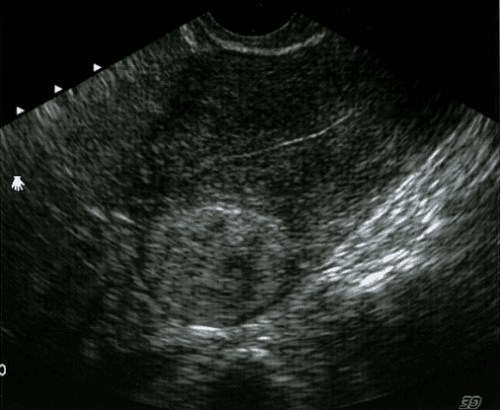

U xơ cơ tử cung trong cơ, u giảm âm do thành phần cơ nhiều hơn xơ trong u